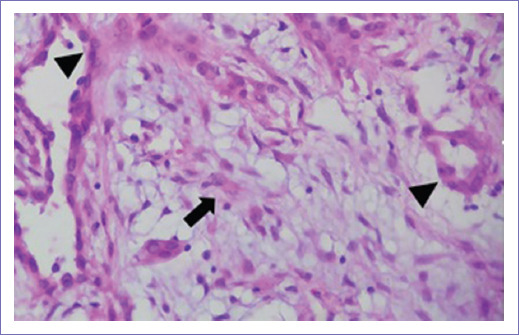

Figura 2 Microfotografía (hematoxilina-eosina 40x). Se observa una lesión tumoral en su mayoría constituida por células mesenquimales (flecha) que en los estudios de inmunohistoquímica fueron reactivas para vimentina y un segundo componente epitelial que forma túbulos (puntas de flecha) que en los estudios de inmunohistoquímica fueron reactivos para citoqueratinas.